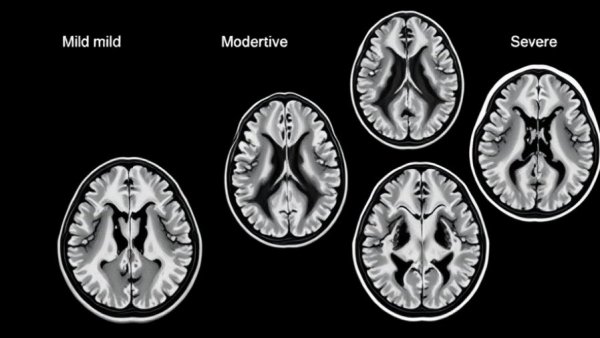

MRI scans showing cerebral small vessel disease progression.

Cerebral small vessel disease (CSVD) stands as one of the most prevalent yet overlooked causes of cognitive decline in older adults. While many may not be familiar with the term, research indicates that the majority of individuals over 60 will show signs of small vessel ischemic changes in their brains, which could consequently affect their daily functioning. Defined as damage to the small blood vessels in the brain, CSVD is an umbrella term encompassing various disorders. Among its manifestations are white matter changes, lacunar infarcts, and cerebral microbleeds — all of which are often detected during routine MRI scans.

Not merely a technical diagnosis, CSVD poses substantial risks. It is closely associated with cognitive impairment, increasing the likelihood of developing vascular dementia and strokes. A staggering statistic mentioned by health professionals reveals that nearly 95% of older adults who've undergone MRI testing exhibit some level of these brain alterations. This makes awareness and understanding of CSVD critical for families and caregivers of aging loved ones.